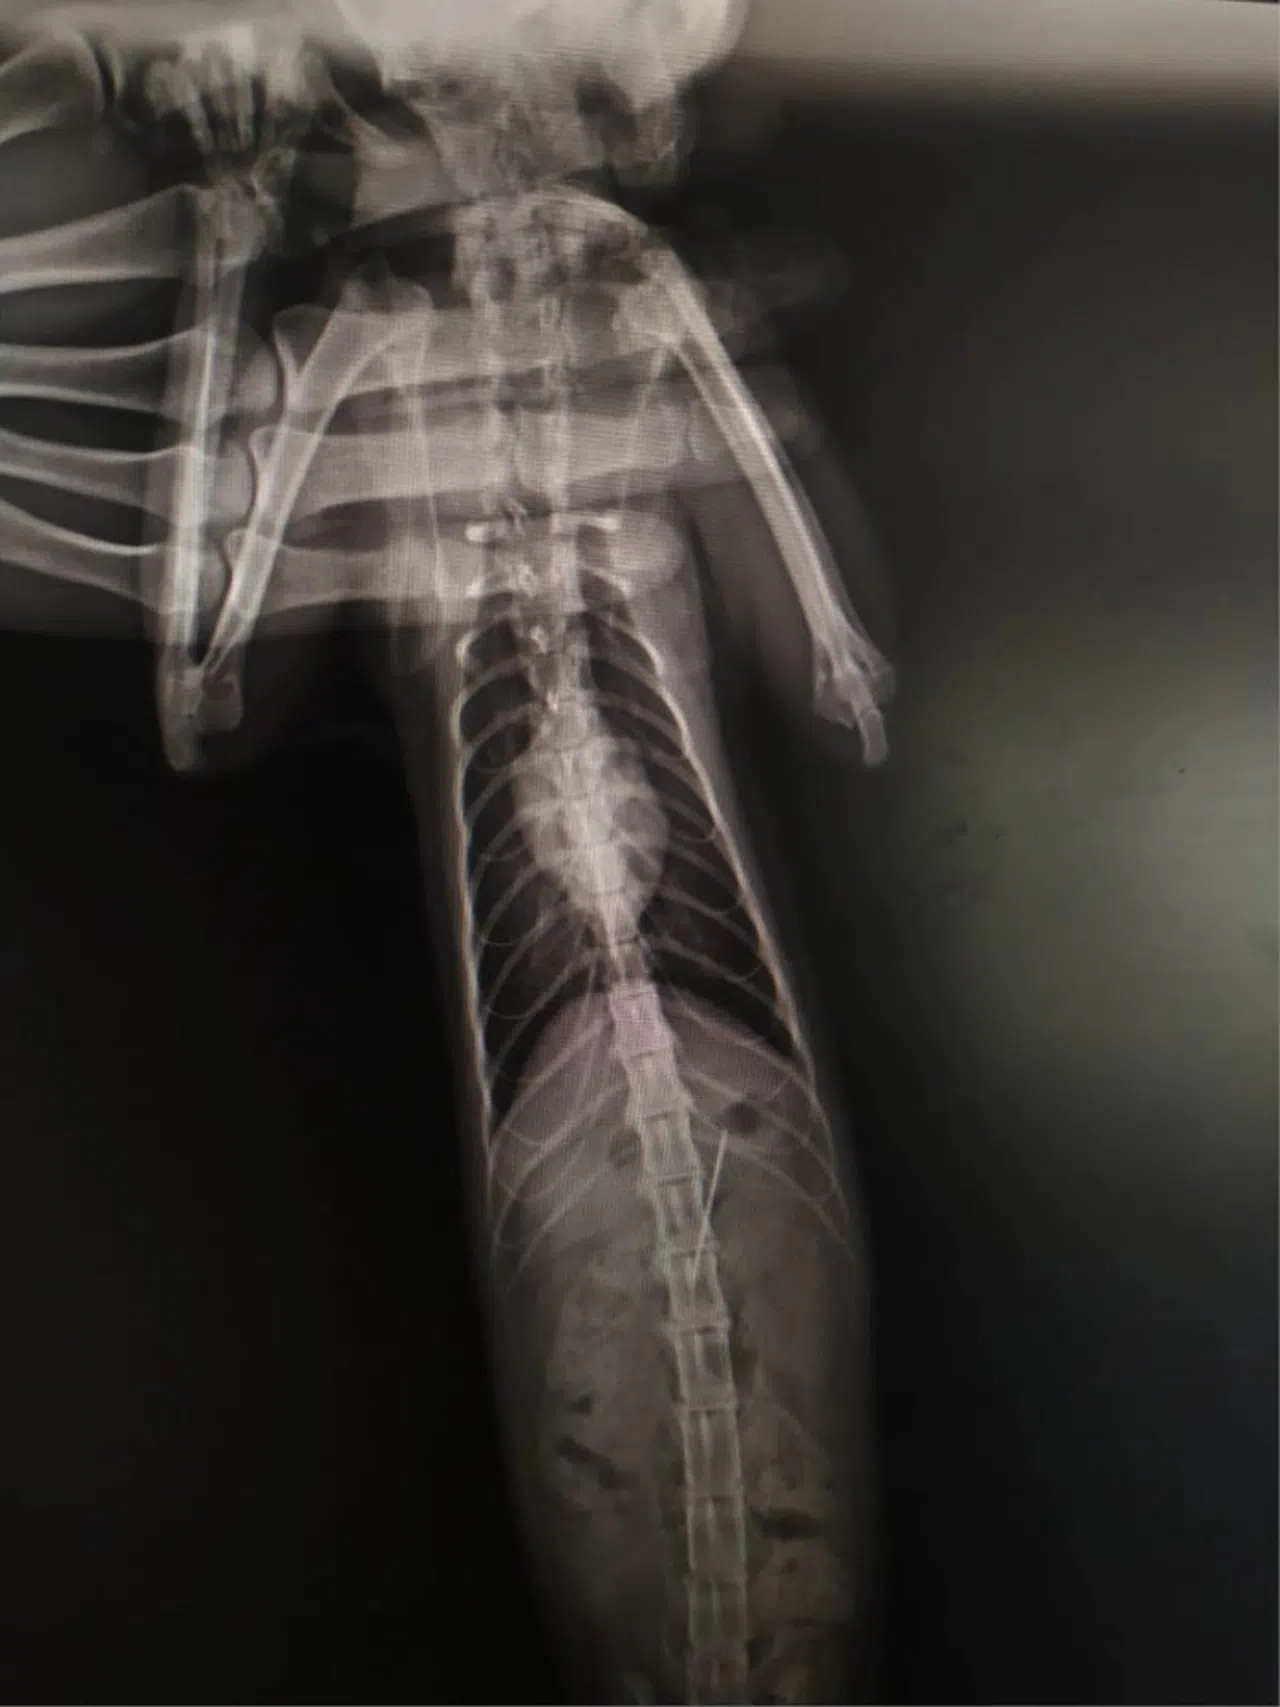

Kentte bulunan özel bir veteriner kliniğinde muayene edilen kedinin röntgeni çekildi.

Kedinin midesinde tespit edilen dikiş iğnesi endoskopiyle çıkarıldı.